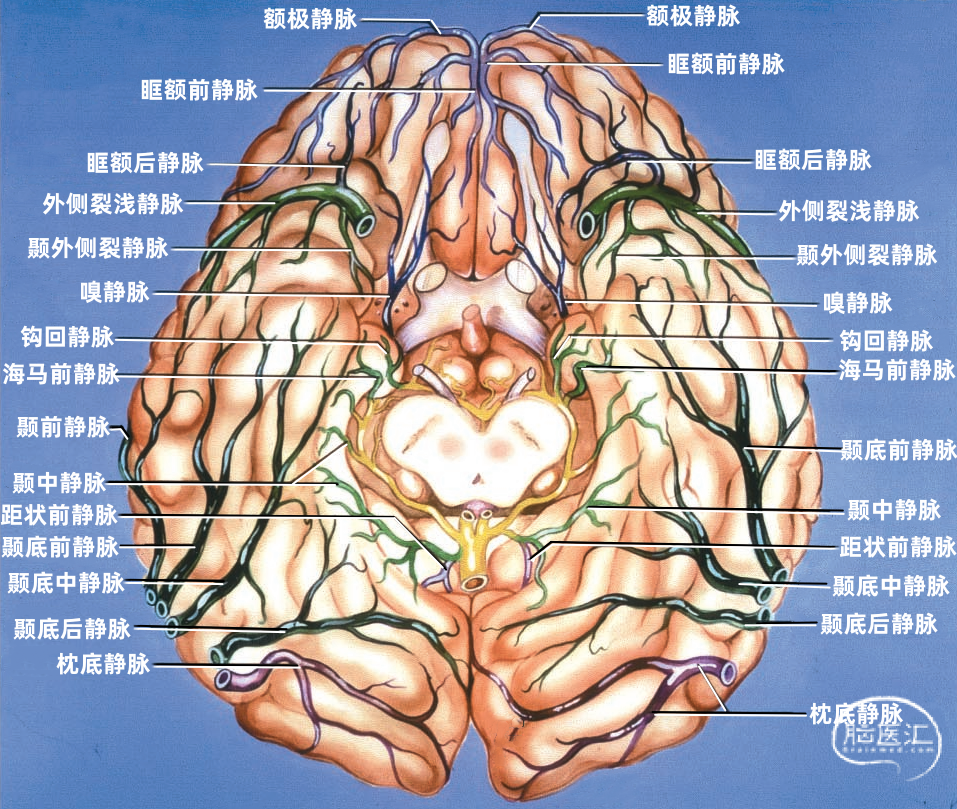

额叶底面(蓝色)由额极静脉、眶额前静脉、眶额后静脉,嗅静脉和终板旁静脉引流。 颞叶底面(绿色)由颞底前静脉、颞底中静脉、颞底后静脉、海马前静脉、钩回静脉、颞内侧静脉、颞外侧裂静脉。

额叶底面的静脉按引流方向由两种蓝色标出:浅蓝色为前组静脉,进入上矢状窦。深蓝色为后组静脉,进入基底静脉前端。额底静脉的前组是眶额前静脉;后组包括眶额后静脉和嗅静脉。 颞叶底面的静脉按引流方向由两种绿色标出:深绿色标注的静脉向外侧走行汇入小脑幕窦。浅绿色标注的静脉向内侧走行汇入基底静脉。向外侧走行的颞底静脉包括颞底前静脉、颞底中静脉、颞底后静脉;向内侧走行的颞底静脉包括海马前静脉、钩回静脉、颞内侧静脉。 枕叶底面只有一支即枕下静脉,由紫色标出,汇入小脑幕窦。大脑内静脉汇入Galen静脉。

▼1.额叶

额叶的引流静脉分为外侧面组、内侧面组、底面组。外侧面组分为上升组,汇入上矢状窦;下降组,引流向外侧裂,进入外侧裂浅静脉。 上升组静脉包括额极、额前、额中、额后静脉,中央前静脉和中央沟静脉。这些静脉可能在回流至上矢状窦前与相邻的底面组、内侧面组的静脉汇合; 下降组由额外侧裂静脉组成。上升组引流的区域大于下降组。 额叶外侧面静脉及其引流区域如下:额极静脉引流额下回、额中回和额上回前部;额前、额中、额后静脉引流额极和中央前回之间的额叶前、中、后部凸面;中央前静脉引流中央前回下部、额下回盖部和邻近的额下、额中和额上回;中央Rolandic静脉引流中央沟附近的中央前回和中央后回;额外侧裂静脉引流额下回和邻近的额中回下部及中央前回下部。 额叶内侧面由弯曲的扣带沟分为内侧区和外侧区。额内侧静脉分为上升组进入上矢状窦;下降组进入下矢状窦或汇入行经胼胝体的静脉,最后进入基底静脉前端。上升组静脉由前内侧额静脉、中内侧额静脉、后内侧额静脉和旁中央沟静脉组成,它们是额上回内侧和邻近扣带回的主要静脉回流,一般向上弯曲走行,在半球上缘向外加入来自半球外侧组的静脉,然后注入上矢状窦。下降组静脉包括胼周前静脉、终板旁静脉和大脑前静脉。 额叶内侧面静脉及其引流区域如下:额前内侧静脉引流额极后方的扣带回和额上回;额中间内侧静脉引流胼胝体膝部前方的额上回和邻近扣带回的内侧面;额后内侧静脉引流胼胝体膝部上方的额上回和扣带回;旁中央静脉引流胼胝体体部上方的扣带回和邻近的旁中央小叶;胼周前静脉为成对的静脉,引流胼胝体膝部和嘴部,以及邻近的扣带回;大脑前静脉引流胼胝体嘴部以下至视交叉上缘之间的区域;终板旁静脉引流胼胝体嘴部下方的终板旁回和嗅旁回区域。 额下静脉组,引流额叶眶面区域,可分为前组和后组:前组流向额极注入上矢状窦;后组引流向后,在外侧裂内侧集中于前穿质表面,形成基底静脉。前组由额眶前静脉和额极静脉组成;后组由嗅静脉和额眶后静脉组成。 额下静脉及其引流区域如下:额眶前静脉引流直回前部和眶回前内侧部;额眶后静脉引流额叶眶面后部;嗅静脉引流嗅沟及其邻近的直回和内侧眶回。

下图示额叶眶面,由额极静脉、额眶前静脉、额眶后静脉、嗅静脉引流。额眶前静脉汇入上矢状窦前部或其分支。额眶后静脉注入前穿质下方的静脉,形成基底静脉的前端。

嗅静脉、终板旁静脉、大脑前静脉和额眶后静脉汇合于基底静脉前端。

下图示左侧前穿质下方区域的放大观。嗅静脉、大脑前静脉、额眶后静脉、外侧裂深静脉汇集形成基底静脉。脑室下静脉在大脑脚后缘汇入基底静脉。

▼3.颞叶

颞叶静脉划分为:引流颞叶凸面的外侧组和引流颞叶底面的下组。 颞叶外侧组静脉还分为上升组,行向外侧裂。下降组,注入颞叶下方的静脉窦。上升组由颞外侧裂静脉组成,下降组由颞前、中、后静脉组成。 颞外侧静脉组及其引流区域如下:颞前静脉引流外侧面前1/3,颞上回除外;颞中静脉引流颞叶凸面中部;颞后静脉引流颞叶凸面后1/3,有时包括角回和顶叶前部;颞外侧裂静脉引流从颞极到外侧裂后端的颞上回。 颞下静脉分为:外侧组引流入小脑幕前外侧的窦;内侧组沿颞叶内侧缘,流入基底静脉。外侧组由前、中、后颞底静脉组成,颞底静脉好像放射状从枕前切迹发出,经过颞叶的下面。内侧组由钩回静脉、海马前静脉和颞叶内侧静脉组成。颞极附近基底面通常由颞外侧裂静脉引流。 颞下静脉及其引流区域如下:颞底前静脉引流颞底前1/3、颞枕回和邻近的海马旁回;颞底中静脉引流颞叶下面中1/3;颞底后静脉引流颞叶底面和枕叶前部;钩回静脉引流钩回和邻近的海马旁回:海马前静脉引流钩回后部和邻近的海马旁回;颞内侧静脉引流脑干上部旁基底池边缘的海马旁回。

下图示颞叶底面。颞叶底面的前部由颞外侧裂静脉引流,并汇入外侧裂的静脉。右侧颞底静脉汇入靠近横窦内侧的小脑幕窦。 正常情况下由左侧前、中颞底静脉引流的区域,主要由一条沿着颞叶底面长轴向后走行的长干引流,且汇入小脑幕窦。黄色和红色箭头为汇入右侧和左侧小脑幕窦的静脉末端。

下图示汇入小脑幕窦的颞底静脉。红色箭头指示左侧汇入小脑幕窦属支的颞底长静脉。右侧颞底静脉汇入有多个属支的右侧小脑幕窦。

枕叶的引流静脉分为外侧组、内侧组和底面组。引流颞叶和顶叶后部的静脉可引流枕叶前部。事实上,枕叶外侧面的引流静脉通常行向前方,而不是后方,这就使得在窦汇前方4~5cm的范围内没有枕叶外侧面的静脉直接引流入上矢状窦,枕叶内侧面后部同样如此。 枕叶内侧面由距状前、后静脉引流。距状前静脉(也称为枕内侧静脉)引流楔叶和舌回的前部,距状后静脉引流距状裂的后部。 枕叶底面由枕下静脉引流。枕基底静脉起自舌回下外侧部、邻近的颞枕区和颞下回连接的属支。它向前外侧走向枕前切迹,而且经常在注入小脑幕外侧窦之前与颞基底后静脉汇合。少数静脉向前内侧走行注入基底静脉。

构成蝶骨嵴组(上图 红色)的桥静脉走行于蝶骨内表面的静脉窦。包括外侧裂浅静脉的终末支(包括额外侧裂静脉、顶外侧裂静脉和颞外侧裂静脉)和少数外侧裂深静脉,引流外侧裂附近的额叶、颞叶和顶叶的静脉血流。 这些静脉一般汇入蝶顶窦或海绵窦,少数进入蝶基底窦或蝶岩窦。 右侧的外侧裂浅静脉(下图 红色)直接进入蝶顶窦或海绵窦前部,而左侧的外侧裂浅静脉更靠后并进入海绵窦外侧部。侧裂深静脉和大脑前静脉也汇入基底静脉前端。颈内动脉行经海绵窦。中颅窝底的硬脑膜窦与脑膜中动脉伴行。

小脑幕组(上图 绿色)的桥静脉汇入行经小脑幕的静脉窦,即小脑幕窦或小脑幕附近的横窦和岩上窦。本组静脉引流颞叶外侧面和底面、枕叶的底面,包括颞底静脉、枕底静脉和来自颞叶外侧面的降静脉,如Labbé静脉。 除Labbé静脉外,这些静脉虽然有可能进入横窦,但大多数围绕半球的下缘汇聚于枕前切迹到达外侧小脑幕窦。而Labbé静脉通常汇入横窦。大脑底面的桥静脉汇入静脉窦之前,经常粘连于与中颅窝底硬膜和小脑幕表面。 从外侧面引流入小脑幕窦的静脉包括颞前静脉、颞中静脉、颞后静脉和Labbé静脉。

从下表面引流入小脑幕窦的静脉包括颞底前静脉,颞底中静脉、颞底后静脉和枕底静脉。 内侧小脑幕窦接受来自小脑的静脉血流,并加入直窦。基底窦位于斜坡。 大脑镰组(上图 紫色)由直接或经由大脑内静脉、基底静脉和大脑大静脉汇入下矢状窦或直窦的静脉构成。汇入直窦的静脉(上图 紫色)或其属支,引流胼胝体附近部分的额叶、顶叶和颞叶内侧部,此组静脉的引流区域大致相当于大脑边缘叶,包括终板旁静脉,额眶后静脉、嗅静脉、胼周前静脉、胼周后静脉,钩回静脉、海马前静脉、颞内侧静脉和距状前静脉。